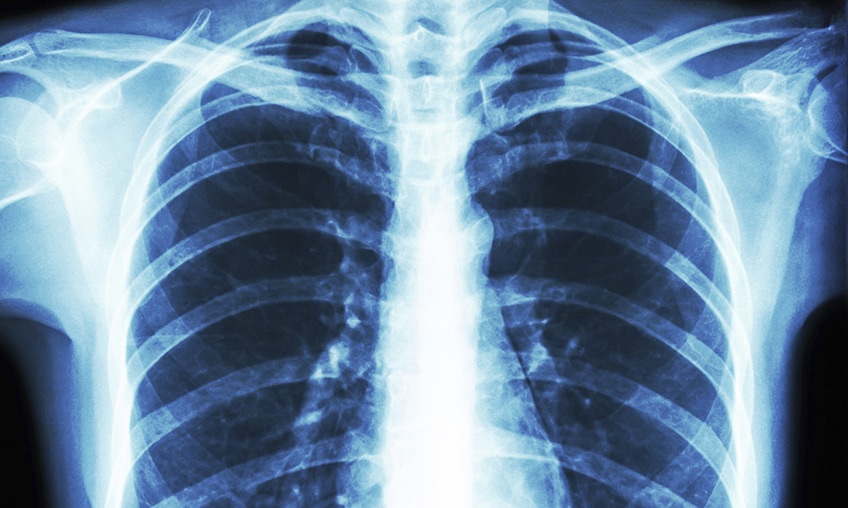

بیماری لژیونر یک شکل شدید ذاتالریه است که ناشی از استنشاق باکتریها موجود در قطرات کوچک یا بلعیدن اتفاقی آب حاوی باکتری لژیونلا است.

گرچه اغلب افراد با مصرف آنتیبیوتیک از بیماری لژیونر بهبود پیدا میکنند، برخی از بیماران- از جمله بیماران دچار نفصان ابمنی یا افراد مبتلا به بیماریهای مزمن ریوی در صورت دچار شدن به عفونت با باکتری لژیونلا ممکن است دچار عوارض مرگبار شوند.